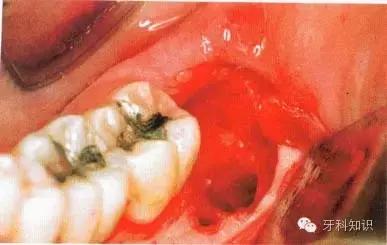

例二

a下颌第三磨牙阻生。代表牙槽窝深度的红线表明从牙槽嵴顶到釉牙骨质界间在近中颊角方向上的距离。考虑到患者的年龄,阻生牙牙槽窝的近中骨壁较容易以第二磨牙牙根旁的硬骨板为基础分化再生。因此,该患者第二磨牙牙槽骨修复重建的预后较好

b阻生牙(牙合)面上覆盖的软组织较完整,牙槽窝与口腔不相通。切口起点应位于颞肌嵴黏膜,前庭沟的舌侧,朝向距离第二磨牙远中面15 mm外缘处向前切开

c翻开黏骨膜瓣显露牙槽嵴。图中已将黏骨膜瓣翻开,在舌侧开窗去骨显露阻生牙的远中颊尖,再通过装在机头上的外科圆钻去除覆盖于(牙合)面的骨质

d 将牙冠颊侧大部分显露至釉牙骨质界时方能较全面地认识该阻生牙在牙槽窝内的位置。根尖片只能显示该阻生牙在(牙合)面的投影而不能显示其颊舌向倾斜的情况。在低位舌侧近中阻生时,阻生牙同时与邻牙牙根的远中壁和舌侧骨板相接触,故舌侧骨板必然较为薄弱甚至被穿透(出现骨开窗)